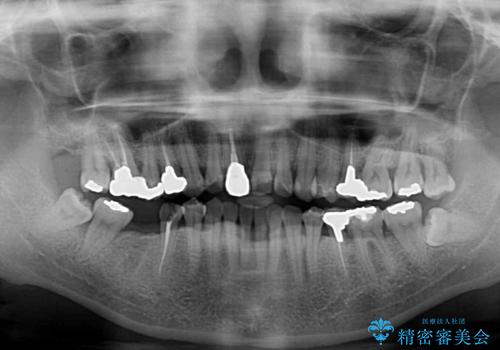

- 右下の欠損部の治療を希望して来院された患者様です。

部分矯正を行った後にインプラント埋入と手前の歯の根管治療を行い、その後補綴治療を行うこととしました。

治療途中より、上の歯や反対側の銀歯、上顎前歯の色合いや下顎前歯のデコボコが気になってきたため、全てを治療することとしました。